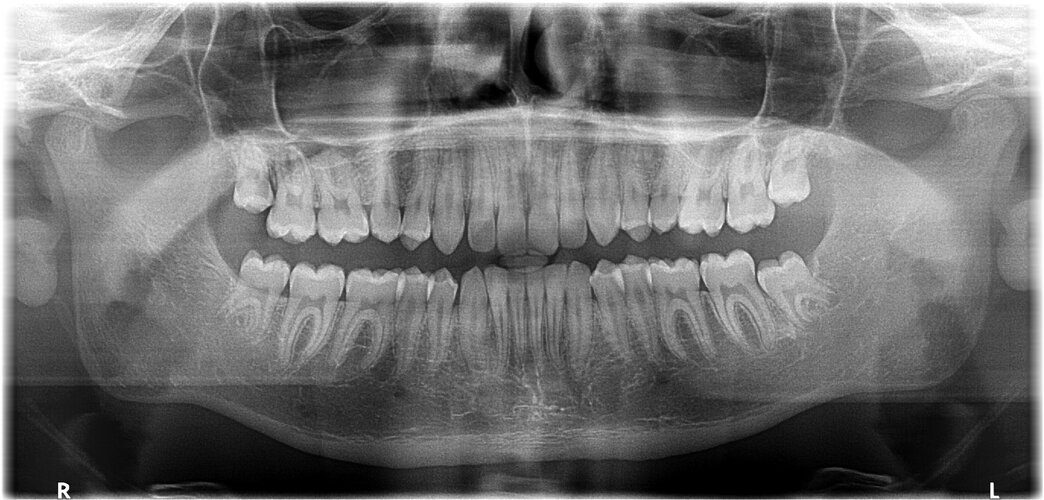

@Loruki are my teeth fucked? my wisdom teeth are breaking through currently

• jaw-panorama-but-i-changed-the-name-of-the-file.JPG